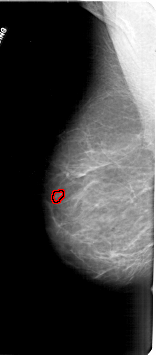

FILE: A_1711_1.LEFT_CC.OVERLAY

TOTAL_ABNORMALITIES 1

ABNORMALITY 1

LESION_TYPE MASS SHAPE LOBULATED MARGINS CIRCUMSCRIBED

ASSESSMENT 4

SUBTLETY 3

PATHOLOGY BENIGN

TOTAL_OUTLINES 1

BOUNDARY

LEFT_CC LINES 6001 PIXELS_PER_LINE 3091 BITS_PER_PIXEL 12 RESOLUTION 43.5 OVERLAY